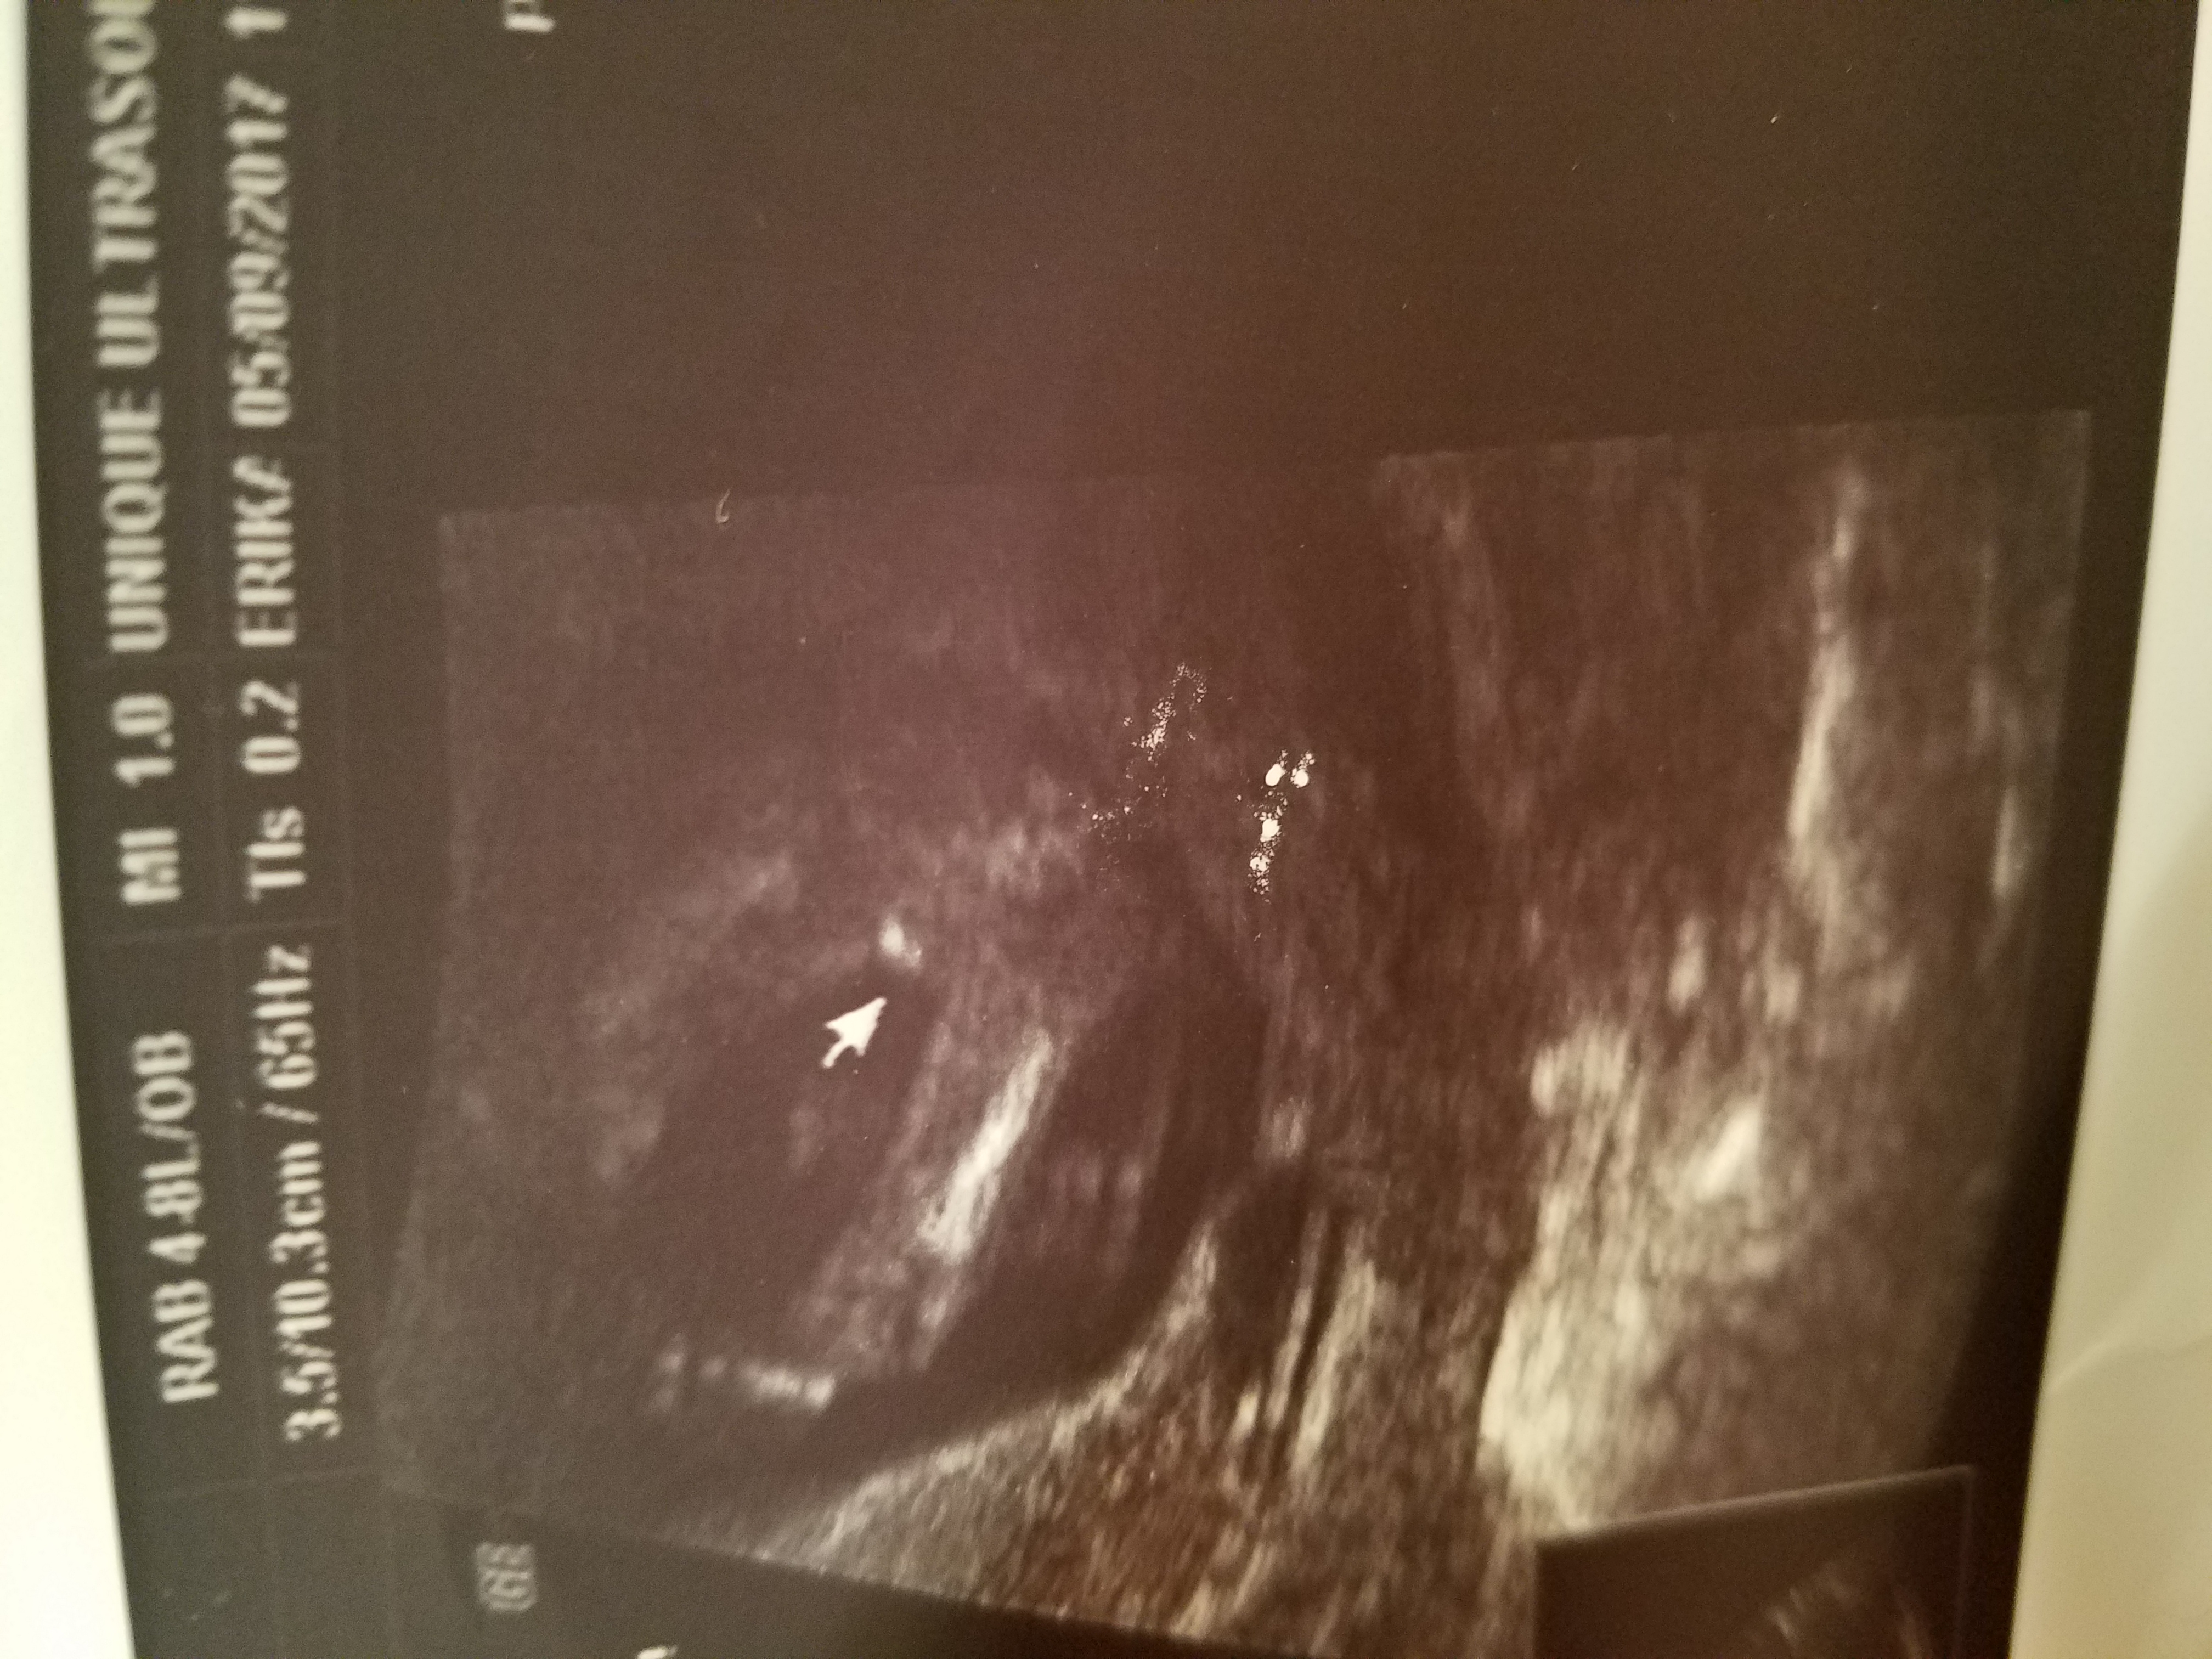

I had an ultrasound at 13 weeks 5 day at an elective u/s place the baby had legs crossed at ankles whole time, took the technician about 20 minutes to see, at first she said he then she said girl. She didn't give me a side picture only a potty shot. Was wondering if she was correct or if it could be wrong since baby had legs crossed at ankles. T.i.aAttachment 36292Attachment 36292

Girl. I saw the exact same with my daughter at 12+5 weeks.

Girl. My DD's potty shot looked like that too at 13w3d. I know they aren't always reliable, but my 3 boys' never looked like that!!